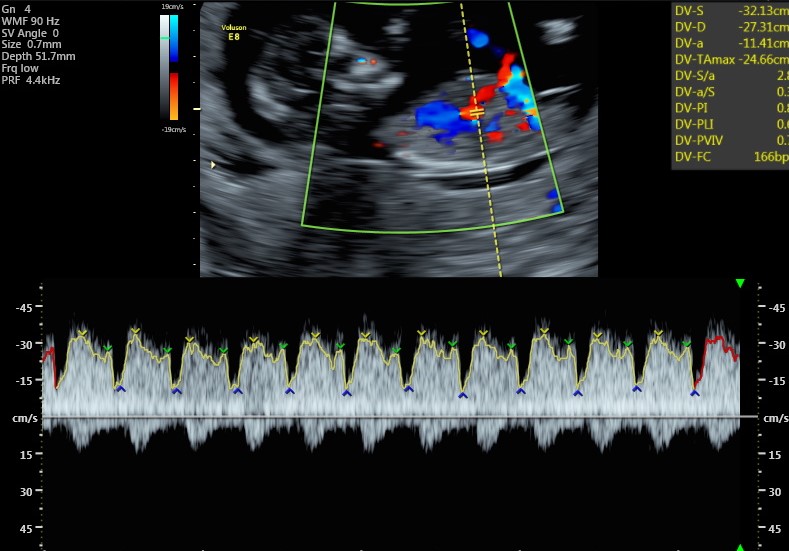

Questa valutazione può essere integrata da quella del dotto venoso (un piccolo vaso a livello del fegato che ci descrive la funzionalità cardiaca), la presenza dell’osso nasale (in medicina fetale avere un naso di una certa importanza è una cosa rassicurante) e l’assenza del rigurgito della valvola cardiaca tricuspide.